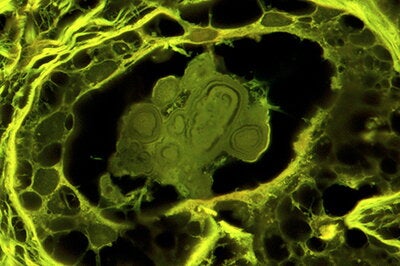

The researchers found that the calcifications were made of amorphous calcium phosphate, a mineral with the ability to shapeshift and rearrange, though it had long been assumed to be the crystalline calcium phosphate type found in bone, hydroxyapatite. The team analyzed the layers of the ACP deposits to trace how they began as small spherules that coalesced into nodules. The nodules then entombed cells and incorporated other molecules, such as proteins, waxy substances and cholesterol.

The shape and progression of calcification differed in BBD and DCIS samples. For example, BBD had more spherical nodules with concentric layering, while cancerous calcifications tended to be more elongated and irregular. Some cancerous nodules also showed progression similar to fossilization characteristic of petrified wood, Fouke said.

“The types of ACP nodules we saw were completely unknown and establish a brand-new classification scheme between BBD and DCIS,” Fouke said. “Each has a different genesis and history of formation, reflecting changes in breast physiology that in turn correlated strongly with whether a biopsy sample was designated benign, possibly benign or suspicious.”